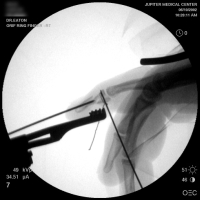

| A wire was passed through the dorsal proximal pin track and then around the palmar pins. After reduction and tightening this wire, the pins were advanced to engage the dorsal cortex. |

| Wiring was used to offset the strong pull of the flexor insertion. |

| All pins were cut below the surface of the skin. |